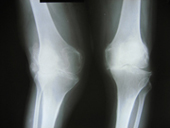

Arthriis of both hips pre op Arthriis of both hips post op Arthritis knee valgus deformity pre op Arthritis knee valgus deformity post op